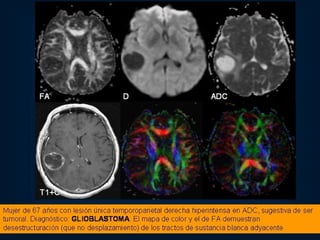

GLIOBLASTOMA

GLIOBLASTOMA MULTIFORME Constituye el 25% de los tumores intracraneanos. Mayor incidencia entre los 40 a 60 años. Tienen un promedio de sobrevida de 8 meses.  Son más frecuentes en el varón. Lesión heterogénea, con efecto masa, gran edema, realce anular, áreas de necrosis, hemorragia. Pueden localizarse en cualquier región del SNC: lóbulos frontales, temporales.

RM Imágenes más nítidas. Diagnóstico, estudio y control de lesiones tumorales en el SNC. Observar: masa tumoral, edema, quistes, hemorragia, calcificación intratumoral, ubicación de la vasculatura. Control post-radioterapia. Muy útil en : T. de tallo y fosa post. Medios de contaste: gadolinio.